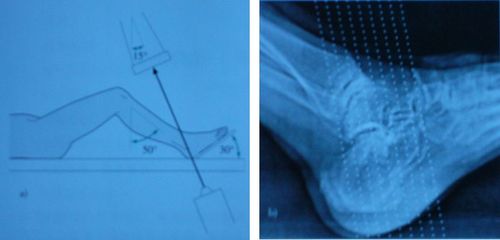

跟骨gissane角

跟骨gissane角,gissane角

gissane角

bohler角gissane角

Bohler角